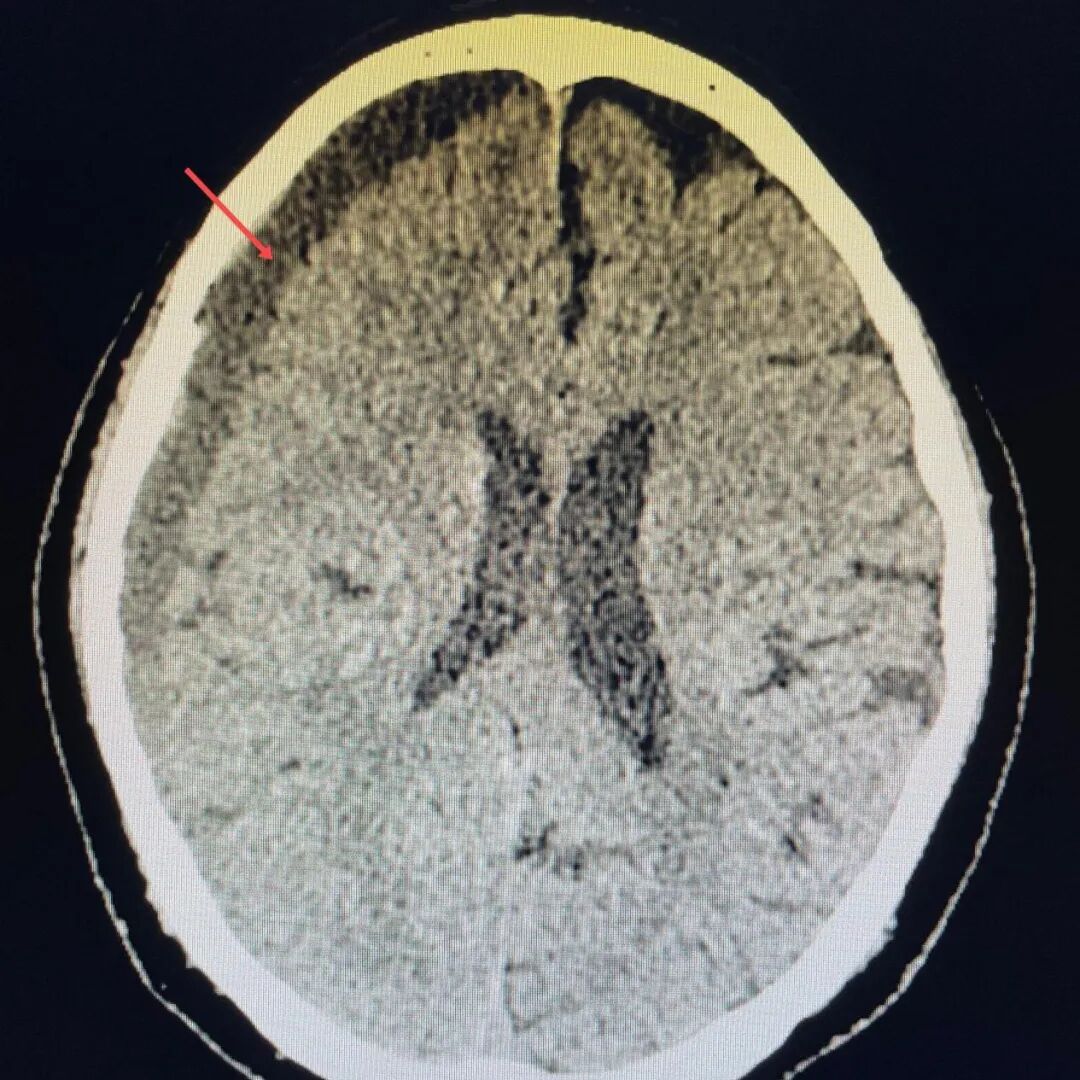

头部撞伤别大意!这种“颅内刺客”专盯老年人